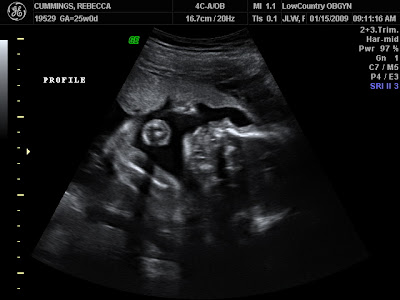

Big stretch at 20 weeks

Our little girl has a name full of meaning..... Meet Maryn Amelia Cummings!!! Mac's grandmothers name is Mary and my grandmothers name is Marian so Maryn is a combination of two very special and influential women in our lives. Amelia is sort of a combination of my late grandmothers name which is Amalia and my middle name Emily. Usually its the mom who gets excited and conscious about a southern little girls initials because we love to monogram everything down here in the south but Mac is most ecstatic. Her initials spell MAC, which is of course how Mac got his name to begin with...Michael Austin Cummings. So...we will soon have a Big Mac and a junior Mac in our home:) Here are Maryn's first glamour shots!!